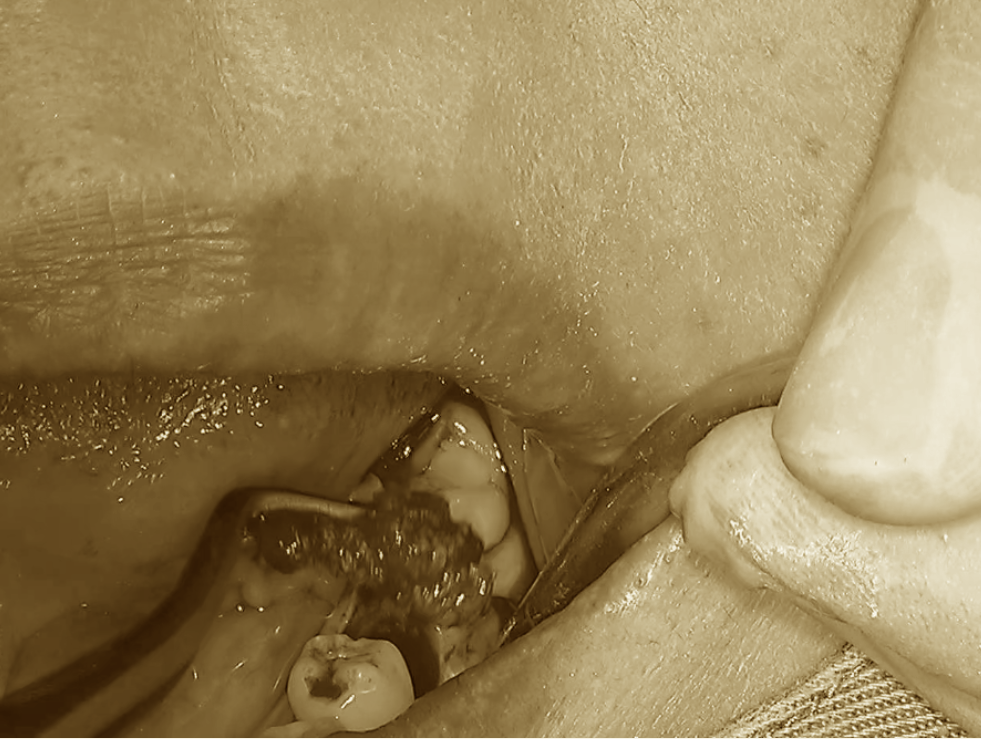

まずは、事前に採取しておいた自家骨を

形成済みの移植床へ丁寧に填入していきます。

続いて、移植する歯の準備です。

歯根表面に再生療法製剤であるエムドゲインを塗布し、

速やかに移植床へと植立します。

適切な位置に収まっていることを確認したうえで、

縫合により固定を行います。

さらに、安定性を高めるために

医療用接着剤を併用し、二重の固定を行います。